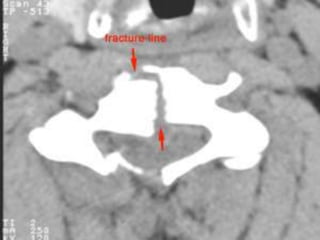

CT IMAGE

DENS

The image through the lateral part of C2 nicely shows, that the fracture runs

through the body of C2, i.e. a type III odontoid fracture.

The posterior dura is in a normal position, but the anterior dura is displaced

(arrow).

Showing Central location of spinal cord injury